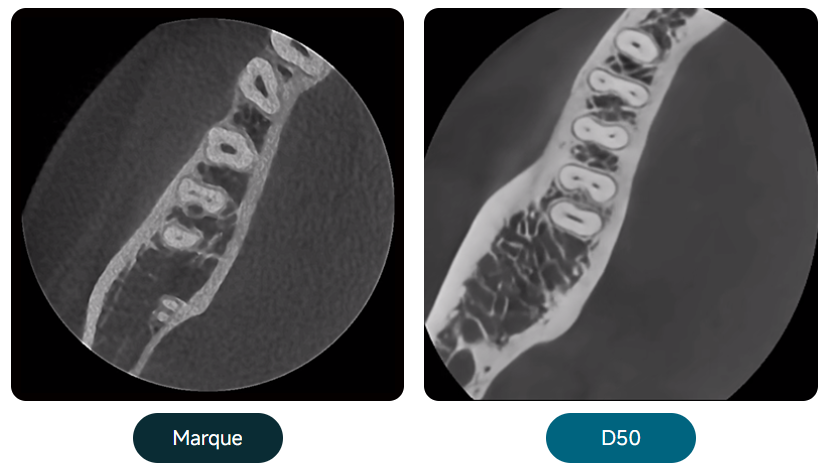

Algorithme de réduction des artefacts métalliques